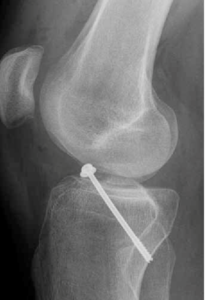

Artroscopia

Es una de las técnicas más empleadas actualmente en nuestro ámbito. Se utiliza para intervenir dentro de las articulaciones mediante una cámara que permite la visión y una serie de instrumentos para tratar la patología. Un tipo especial es al tenoscopia o cirugía endoscópica, que es visualizar tejidos internos a través de una cámara, como tendones o zonas periarticulares.